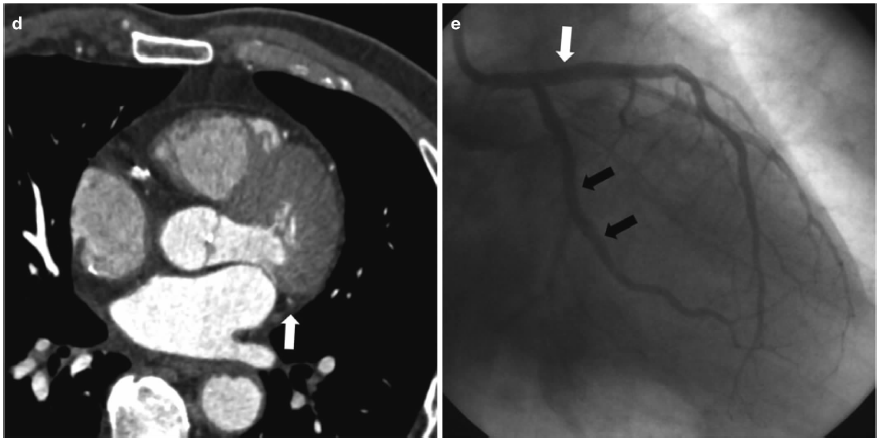

ct如何看冠状动脉狭窄高清图谱详解要点